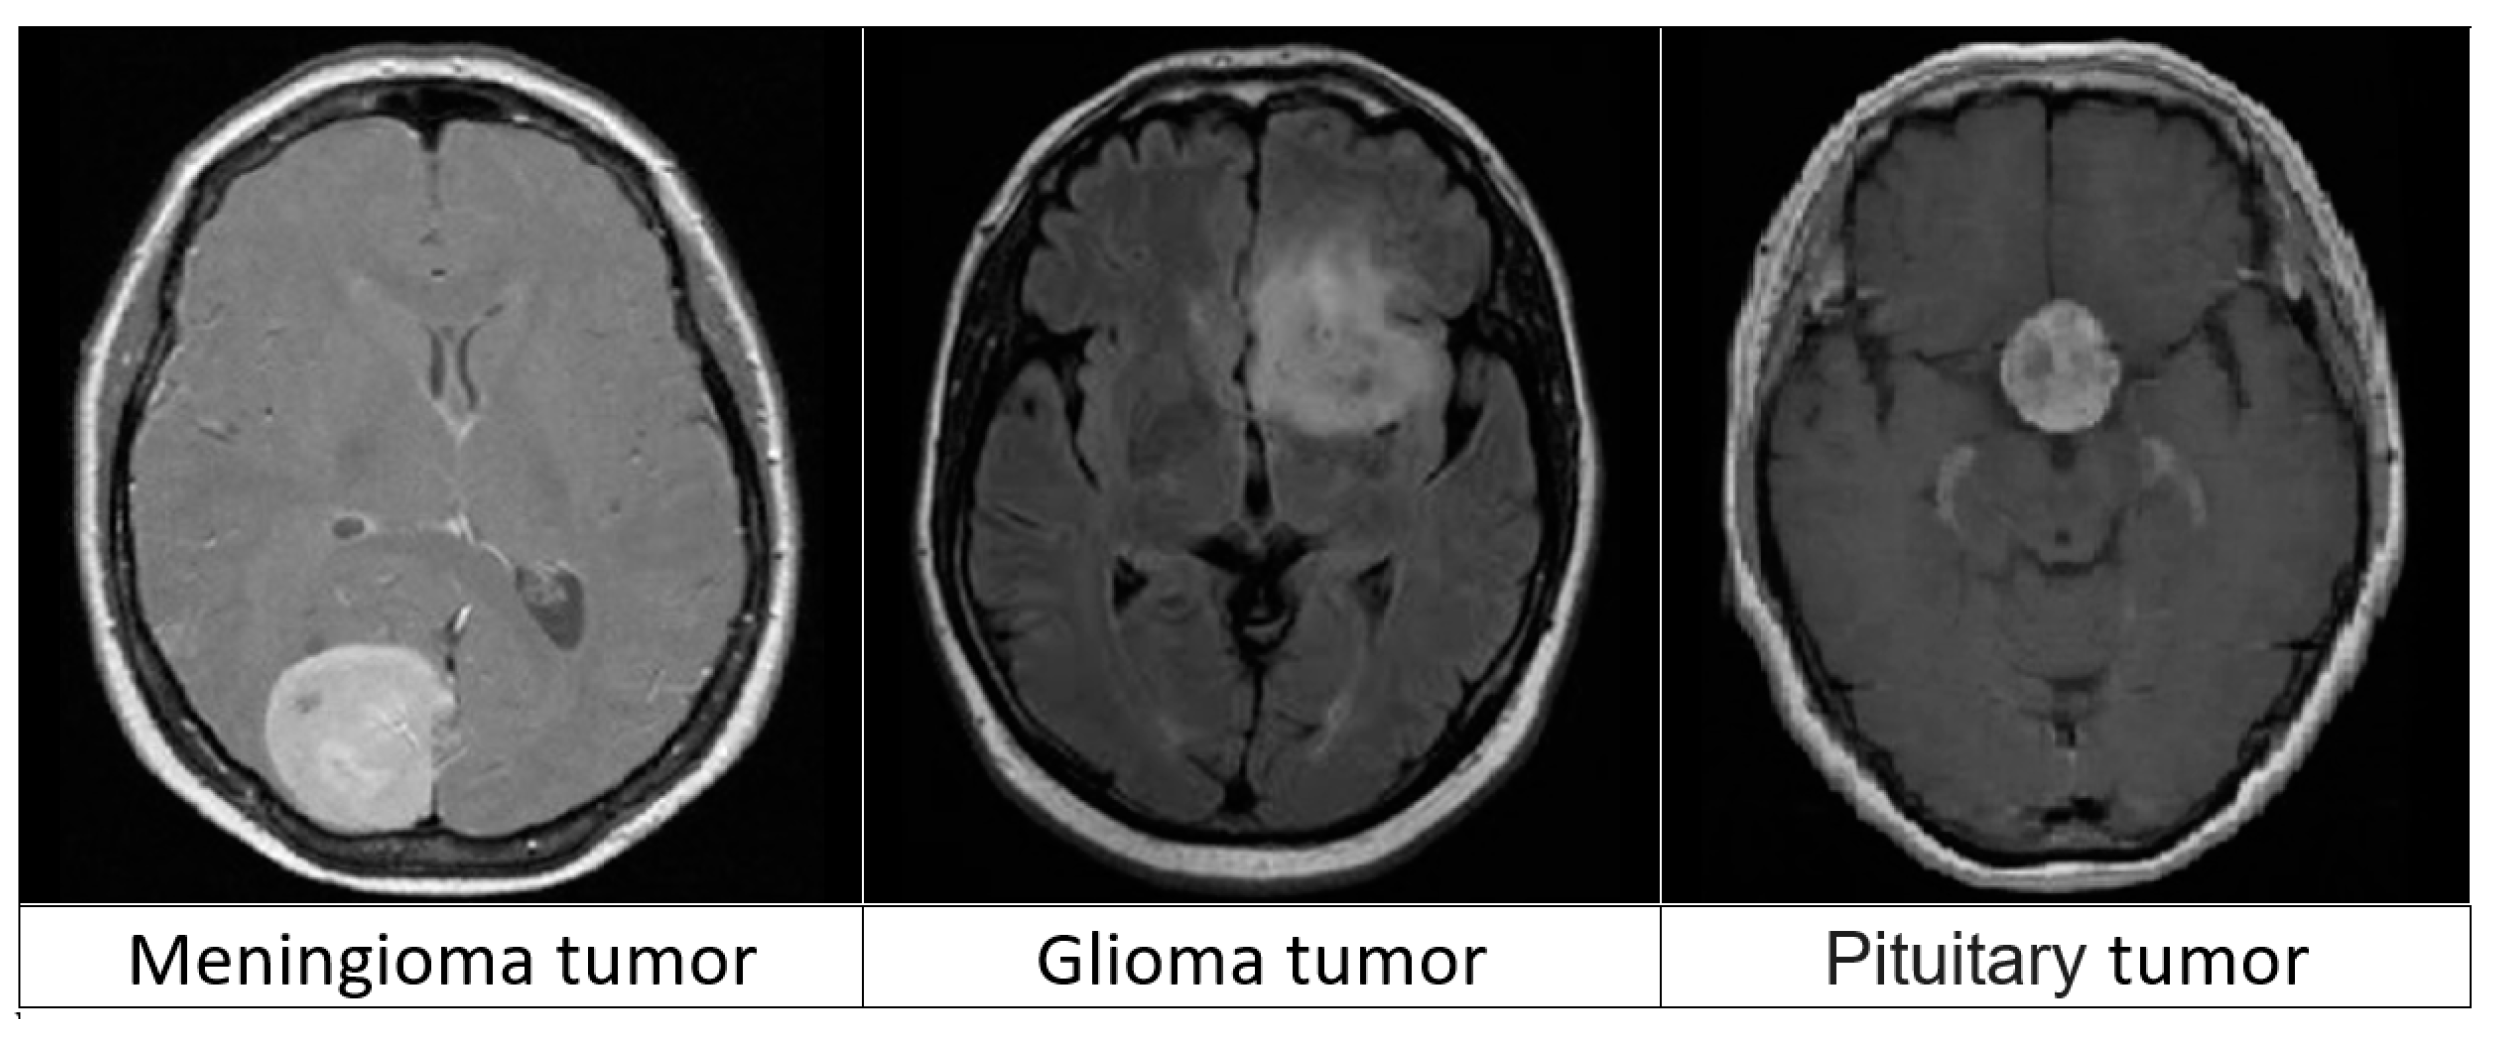

3. System Model

4. Dataset Description